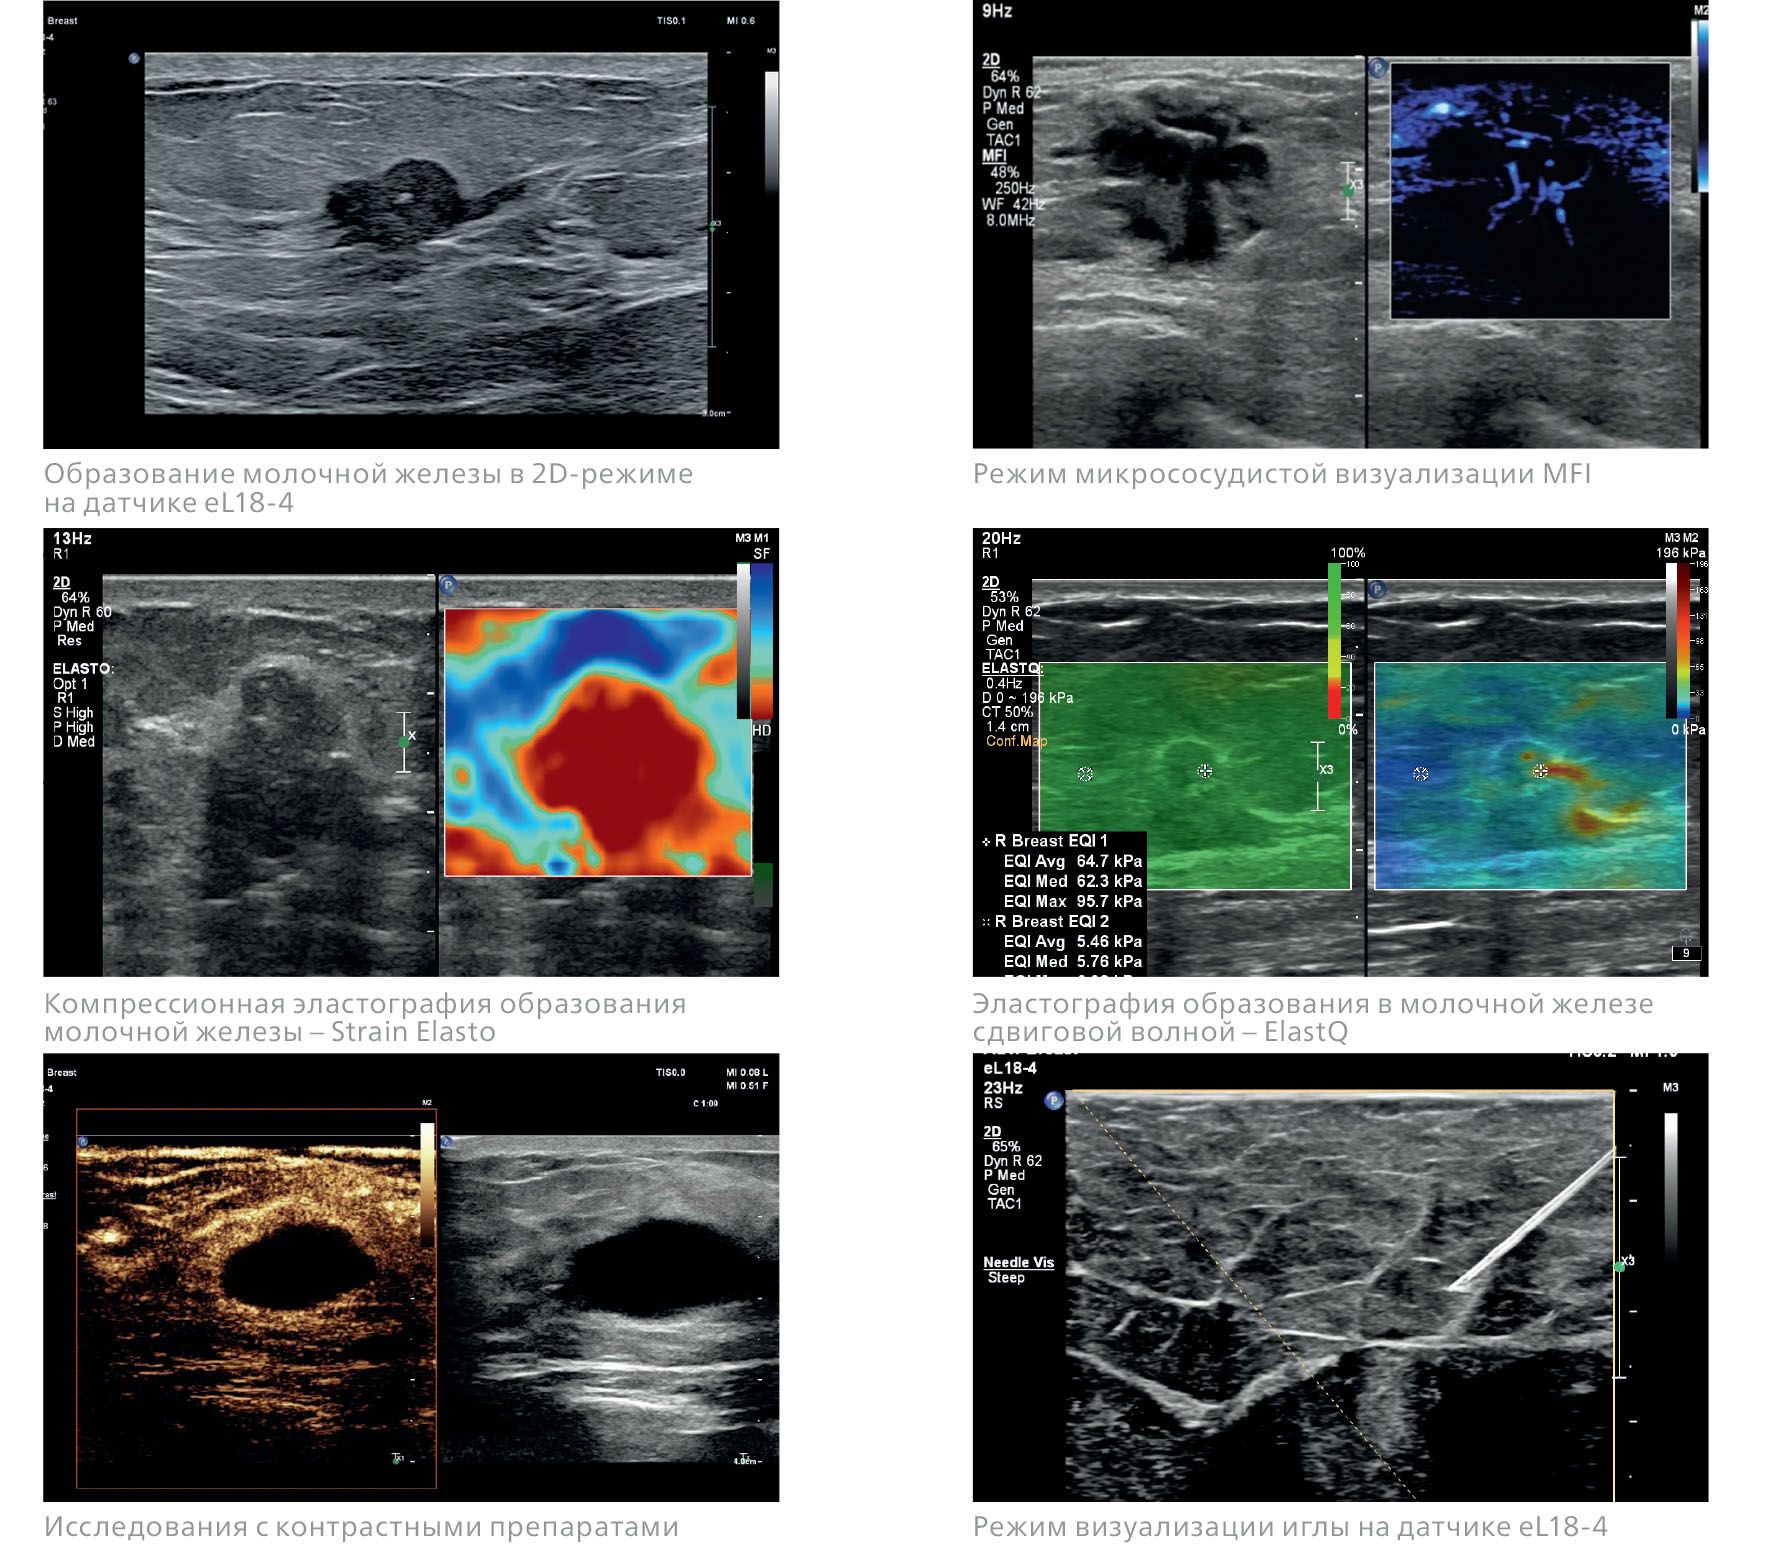

УЗИ для сканирования молочных желез

Ультразвуковое исследование — безопасный метод, не использующий ионизирующее излучение. Оптимален как первичный способ оценки у молодых женщин (до 40 лет) с плотным типом строения железы, как дополнение к маммографии (после 40) и в качестве скрининга для раннего выявления патологий. Ультразвуковое исследование наиболее эффективно при скрининге небольшой груди, где преобладают железистые ткани. С возрастом железа замещается жиром, который имеет низкую эхогенность и равномерную плотность.

-

Плюсы: высокая доступность, безболезненность и безопасность, возможность проведения процедур неограниченное количество раз, можно выполнять беременным и во время лактации. Отличная дифференциация кистозных образований и возможность оценки состояния лимфатических узлов.

Минусы: зависит от опыта оператора, неэффективен для скринингового выявления микрокальцинатов — раннего признака рака, позволяет оценить только ограниченную область, а не всю железу целиком за один сеанс.

Возможности технологий Philips для исследований в маммологии: Ультразвуковые системы EPIQ и Affiniti обеспечивают качественную визуализацию, поддерживают технологии оценки эластичности тканей, исследования с контрастированием, объемное сканирование и другие современные технологии.